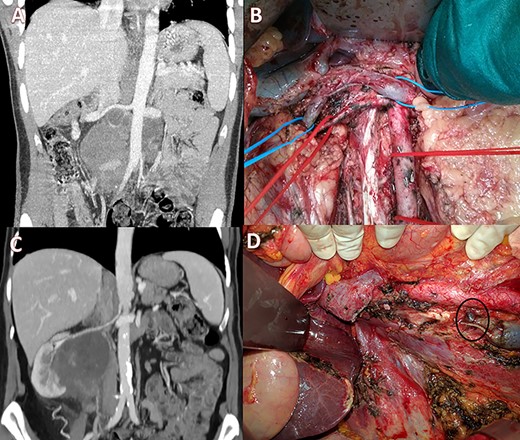

Case 2 was a 23-year-old male with a testicular germ-cell tumor and evidence of pathologically enlarged abdominal and cervical lymph nodes. After surgical excision of the primary tumor and administration of four cycles of Bleomycin, Etoposide and Platinum (cisplatin) (BEP) + four cycles of paclitaxel, ifosfamide and cis-platinum at another institution, the patient was referred to us. CT scan showed stable disease with a large infrarenal inter-aortocaval mass (13 × 10 cm) obstructing the IVC (Fig. 2A). Extensive abdominal lymphadenectomy and resection of the infrarenal IVC without prosthetic replacement was performed (Fig. 2B). Concurrently, ear−nose and throat surgeons performed modified radical left neck lymphadenectomy. The post-operative course was characterized by transient renal failure and moderate anemia requiring blood transfusions and rehydration therapy. The patient was discharged 13 days later and had normal renal function values and no relevant inferior limb edema. Histology confirmed the diagnosis of lymph node metastases of the germ cell tumor.

(A) Pre-operative CT scan with a large lesion involving the IVC; (B) intraoperative view showing ligation of the IVC with renal-vein preservation; (C) coronal CT scan with a huge retroperitoneal space-occupying lesion infiltrating the right kidney and occluding the IVC; (D) intraoperative image after right nephrectomy and IVC resection showing a large collateral lumbar trunk (circle).

Case 3 was a 65-year-old woman with a 9 × 7 cm retroperitoneal mass infiltrating the right kidney and the IVC with radiologic evidence of IVC and right ureteral obstruction (Fig. 2C). Percutaneous biopsy was compatible with angiomyosarcoma. Clinical examination showed no edema of the lower limbs. Neo-adjuvant chemoradiotherapy (doxorubicin + dacarbazine followed by 50 Gy in 25 fractions) was performed. Post-treatment positron emission tomography scan imaging showed stable disease with partial metabolic response. Subsequently, the patient underwent radical resection of the tumor with right nephrectomy and infrarenal IVC resection. No IVC reconstruction was performed and at surgery, venous outflow through a collateral venous lumbar vein was noticed and preserved (Fig. 2D, circle). No major perioperative complications occurred. Post-operative ultrasonography revealed normal lower limb venous pathways and the patient was discharged on post-operative day 11. Histological examination confirmed a leiomyosarcoma grade 2 Fédération Nationale des Centres de Lutte Contre Le Cancer (FNCLCC criteria) with large post-chemotherapy areas of necrosis.